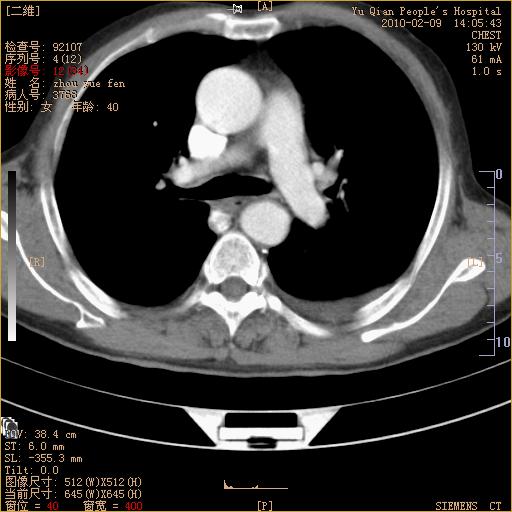

男性,73岁,咳嗽咳血数天,诊为肺ca伴左肺下叶后段阻塞性炎症、肺不张妥否?

右下肺有转移?

左下肺中央型肺癌伴结段形肺不张,左侧胸腔积液,纵隔内见部分增大淋巴结(反应性增生或转移)

左下基底干支气管明显变窄。

左肺下叶基底段支气管狭窄,左肺门增大,左肺下叶团片状病灶。中心型肺癌伴柱塞性炎症可能大,建议支气管镜检查。

左下肺中央型肺癌伴节段性肺不张,左侧胸腔积液,纵隔内见肿大淋巴结

左下基底段支气管变窄。建议进一步纤支镜检查。

1、左肺下叶后基地段肺癌伴阻塞性炎症,左下肺门淋巴结转移。2、左侧胸腔积液。